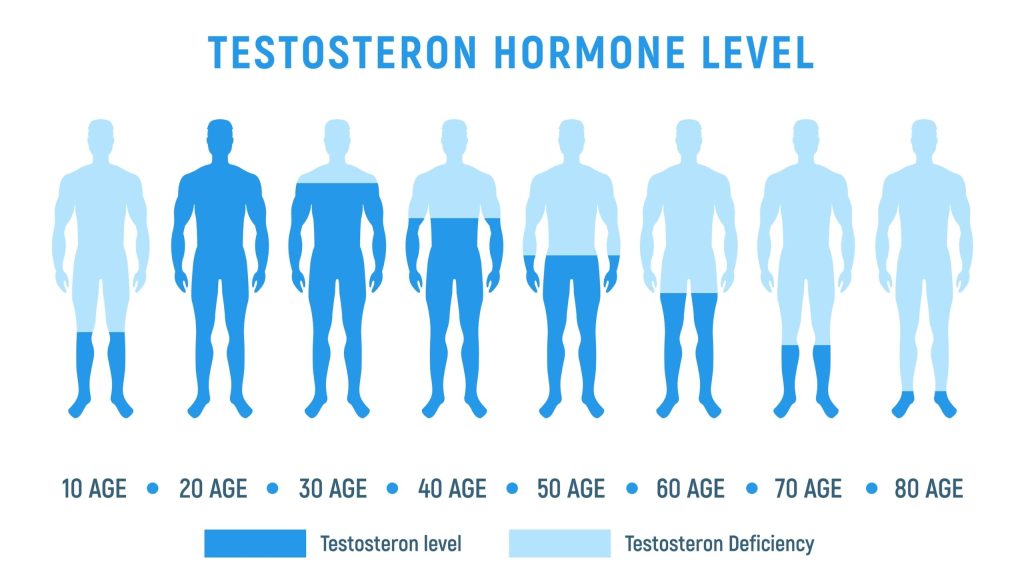

As per a study by the US FDA, in 2009, males with a low thyroid issue can have low testosterone levels. The study shows how more than 55% of males had the same problems at different age groups.

Because testosterone is the main sex hormone in the male body, a low T hormone means problems in getting or maintaining a hard erection longer. In case you have impotence, it is time to use the Cenforce 200 pills.